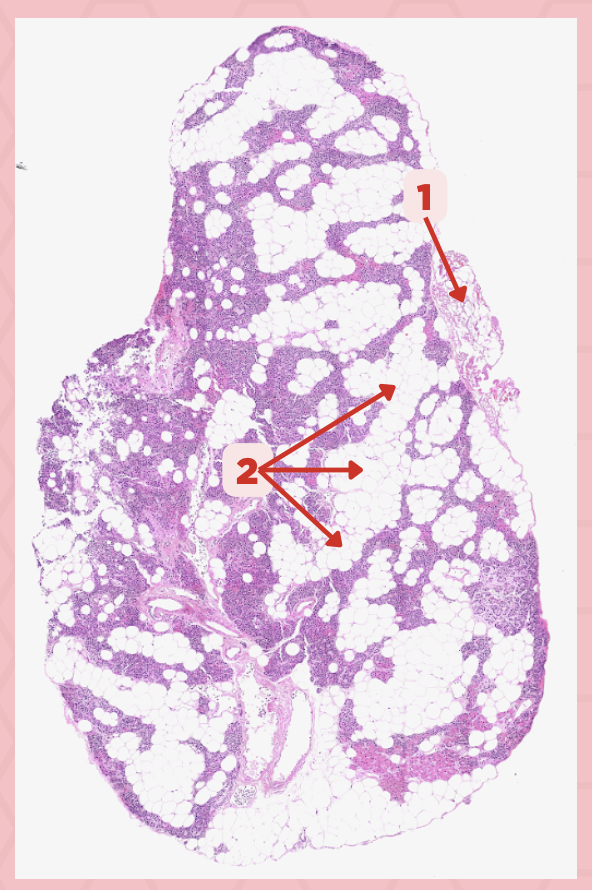

Parathyroid

Identify the specimen.

Chief Cells

Identify the structure labeled as 1. This comprise the majority of cells in the parathyroid gland.

Septa

Identify the structure labeled as 2.

Parathyroid hormones

What hormones are synthesized and secreted by the cell in Pointer #1?

Oxyphil cells

What parenchymal cells in the parathyroid gland only appear shortly before puberty and increase in number with age?

Parathyroid

Identify the specimen.

Chief Cells

Identify the specimen labeled as 1.

Oxyphil Cells

Identify the specimen labeled as 2.

Adipocytes

Identify the specimen labeled as 3.

Capillaries

Identify the specimen labeled as 4.

Newborns

Pointer #2 is hardly present in the parathyroid glands of _____.